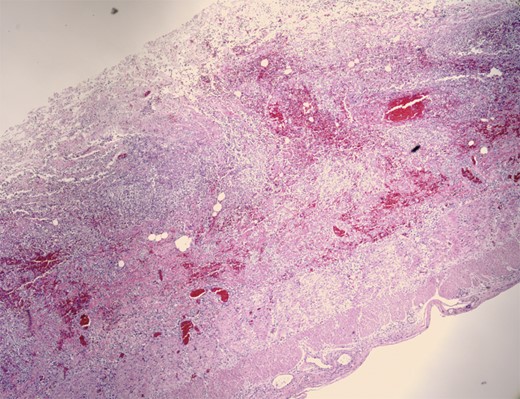

Pathologic evaluation of the resected bowel revealed hemorrhagic, gangrenous bowel (Fig. 1) and granular friable, ulcerated mucosa (Fig. 2). Microscopically, there were areas of transmural bowel necrosis (Fig. 3) and fungi within the bowel wall, artery wall and lumen (Fig. 4). Gomori Methenamine Silver stain was characteristic of Aspergillus species (Fig. 5).

Hemorrhagic bowel with dark purple–black areas of gangrene and foci of serosal fibrinopurulent exudate.